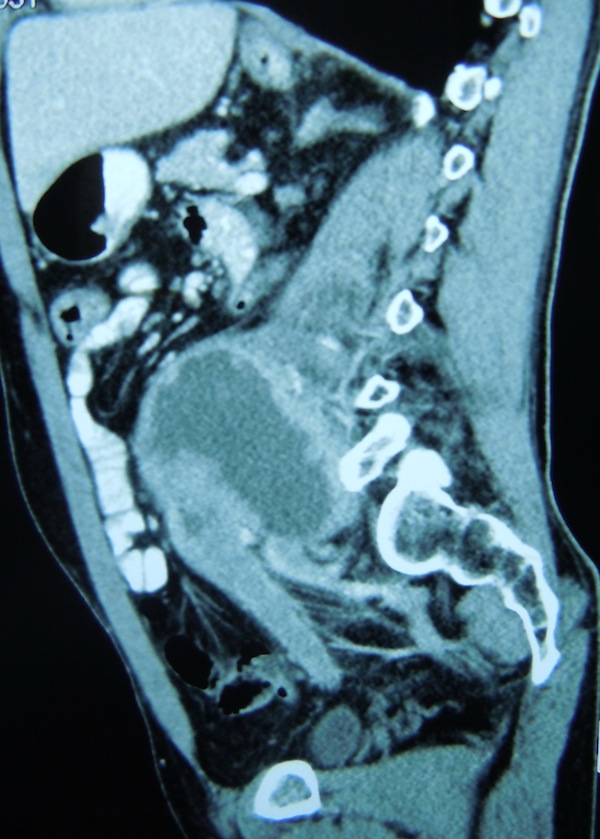

06.06.2013г. – операция: комбинированное удаление рецидива опухоли лоханки левой почки с краевой резекцией левой общей подвздошной вены, резекция стенки мочевого пузыря, резекция ободочной кишки, формирование трансверзоректоанастомоза: Под сочетанной (см. протокол анестезии), в положении на спине, после обработки операционного поля, произведена верхненижнесрединная лапаротомия длиной 30 см по старому послеоперационному рубцу. При ревизии брюшной полости отмечается образование в ложе удаленной левой почки, плотной консистенции, не смещаемое, с вростанием в брыжейку нисходящего отдела ободочной кишки, интимно прилежащее к поджелудочной железе, брюшному отделу аорты, подвздошным сосудам слева, вростающее в левую поясничную мышцу. Выполнена резекция ободочной кишки (30 см) с помощью прямого степлера, сформирован анастомоз по типу конец в конец с помощью циркулярного сшивающего степлера. С техническими сложностями опухоль отделена тупым и острым путем от поясничной мышцы, подвздошных сосудов. С техническими сложностями выполнена мобилизация общей подвздошной вены с краевой резекцией, одномоментной кровопотерей до 1 литра. Выполнена резекция стенки мочевого пузыря с устьем левого мочеточника. Мочевой пузырь ушит двурядным швом. Опухоль, культя левого мочеточника, резецированная стенка мочевого пузыря, резецированная ободочная кишка, лимфатические узлы удалены ad block. Контроль гемостаза, целостности окружающих органов, инородных тел в ране. Послеоперационная рана послойно ушита с выведением ПХВ дренажей из ложа удаленной опухоли через контраппертуру, в малый таз через параректальную область слева. Послойный шов раны, асептическая повязка. Общая кровопотеря 3500 мл.

Гистологическое исследование 12114-78 от 17.06.2013г. (ad block: удаленная опухоль, культя левого мочеточника, резецированная стенка мочевого пузыря, резецированная ободочная кишка, лимфатические узлы): инвазивный умеренно дифференцированный уротелиальный рак высокой степени злокачественности (G2 с участками G3). Рецидив в зоне выполненной нефрэктомии в 2008 г. по поводу рака лоханки левой почки (по клиническим данным). опухоль представлена кистовидным образованием размерами до 16х8х8 см, с собственной толстой фиброзной капсулой толщиной до 3-4 см, в проствете кистовидного образования – множественные обильные очаги разрастания опухолевой ткани. Глубина инвазии опухоли – до 21/2-2/3 толщины ее собственной капсулы, за ее пределы опухоль не проростает. Снаружи кистовидное образование окружено жировой клетчаткой, к нему тесно прилежит удаленный фрагмент толстой кишки. толстая кишка, включая ее края резекции – без признаков опухолевого роста. Культя мочеточника – без признаков опухолевого роста, со склеротическими изменениями. Выявлено 15 прилежащих лимфатических узлов – без признаков опухолевого роста, с реактивным синусовым гистиоцитозом. Гистологическое исследование 12099-113 от 17.06.2013г. (клетчатка из области общих подвздошных сосудов слева): фрагменты жировой клетчатки с лимфатическими узлами (выявлено 12 лимфатических узлов) – без признаков опухолевого роста, с реактивным синусовым гистиоцитозом и с очаговой реактивной фолликулярной гиперплазией).